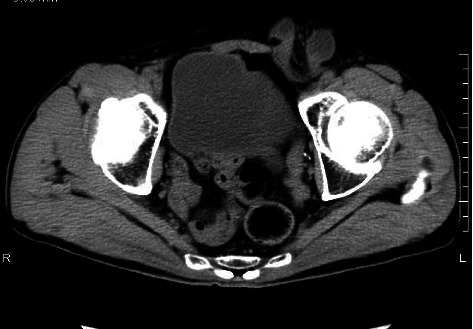

背景:隐睾是新生儿男性最常见的先天性异常之一,大多数在婴儿期诊断并在青春期前手术治疗。在某些情况下,隐睾是在成人腹股沟疝修补时偶然发现的,需要在手术时进行适当的处理。病例介绍:病例1:一名58岁男性因左侧嵌顿疝接受紧急腹腔镜手术。术中发现一例M2型腹股沟斜疝伴精索网膜绞窄。尽管试图用手把睾丸拉下来,但它没有下降到阴囊内,这导致了隐睾症的诊断。切除精索,放置3D网片覆盖疝缺损。病例2:一名33岁的努南综合征患者,表现为右腹股沟局部疼痛和肿胀。腹腔镜检查发现三层腹股沟斜疝,并发现腹腔内睾丸。发现睾丸和精管在腹腔内终止,确认隐睾的诊断。行睾丸切开术,将睾丸皮下固定于阴囊内,并用3D补片修复疝。结论:隐睾合并腹股沟疝行补片修补术的安全性已有文献报道。在术前因疼痛难以触诊的情况下,术中牵拉睾丸有助于区分隐睾症和收缩性睾丸。此外,睾丸切除术可作为一种临时措施,必要时可考虑分期切除。

Background: Cryptorchidism is one of the most common congenital anomalies in newborn males, with the majority diagnosed in infancy and treated surgically before puberty. In some cases, cryptorchid testes are discovered incidentally during inguinal hernia repair in adults, requiring appropriate management at the time of surgery. Case Presentation: Case 1: A 58-year-old male underwent emergency laparoscopic surgery for a left incarcerated hernia. Intraoperatively, an M2 indirect inguinal hernia with omental strangulation of the spermatic cord was identified. Despite attempts to pull the testis down manually, it did not descend into the scrotum, leading to the diagnosis of cryptorchidism. The spermatic cord was excised and a 3D mesh was placed to cover the hernia defect. Case 2: A 33-year-old man with Noonan syndrome presented with localized pain and swelling in the right groin. Laparoscopy revealed an indirect L3 inguinal hernia and incidentally an intra-abdominal testis was found. The testis and spermatic vessels were found to terminate intra-abdominally, confirming the diagnosis of cryptorchidism. An orchiopexy was performed to secure the testis subcutaneously in the scrotum and the hernia was repaired with a 3D mesh. Conclusion: The safety of mesh-based hernia repair in cases of cryptorchidism with concomitant inguinal hernia has been previously reported. In cases where preoperative palpation is difficult due to pain, intraoperative traction of the testis may help differentiate between cryptorchidism and retractile testis. In addition, orchiopexy may serve as a temporary measure, with consideration of staged orchiectomy if necessary.